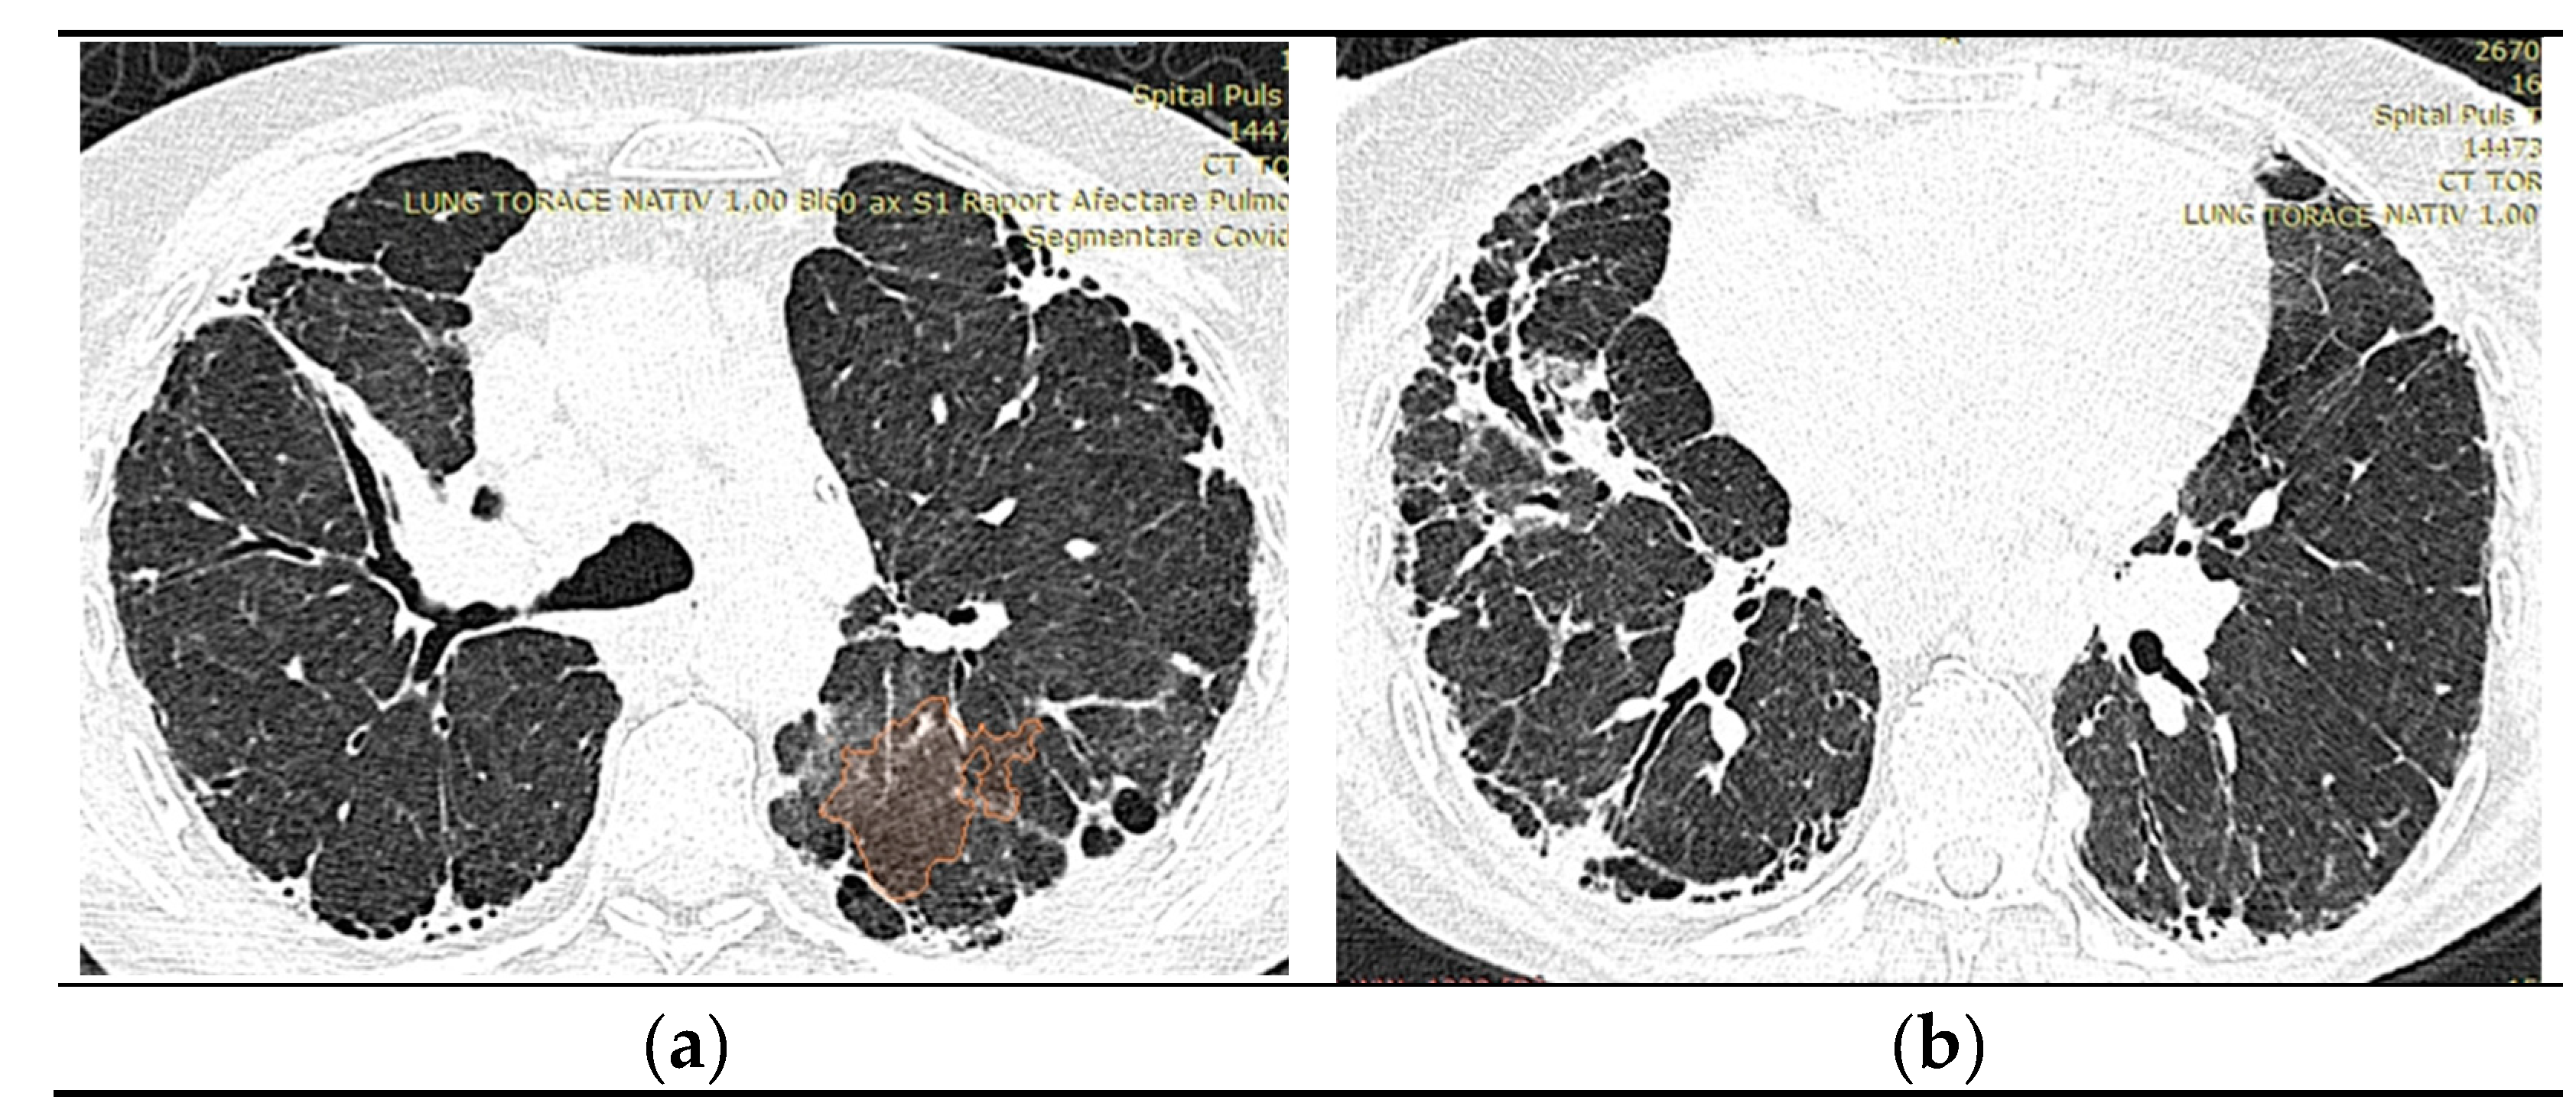

2.1.6. High-Resolution Computed Tomography (October 12th 2022) (Figure 2)

Thyroid gland of normal appearance. Advanced fibrotic changes in both lung fields with septal thickening, architectural disorganization and traction bronchiectasis, the changes being more important at the basal level of the bilateral lower lobes. Small diffuse calcified granulomas bilaterally, without areas of pulmonary condensation. Absence of suspicious pulmonary nodules. Trachea and bronchi with free lumens. Absence of mediastinal masses. Absence of pleural fluid accumulations. Mediastinal adenopathies up to 17 mm perivascular, 16 mm pretracheal at the right, 18 mm left hilar, 15 mm right hilar, and multiple subcentimeter, some with punctate calcifications. Esophagus minimally dilated, with liquid content. Cardiomegaly, pericardial blade up to 18 mm in the right ventricle. Accentuation of dorsal kyphosis. Early degenerative changes in the dorsal spine, without suspicious lesions on the scanned bone segment. Conclusions: Pulmonary fibrosis changes with medium-advanced damage. Pericardial minimum. Esophageal stasis, more likely in the context of achalasia. Bilateral mediastinal and hilar adenopathies, some with calcifications.

Figure 2. a), b): Computed Tomography of the Thorax.